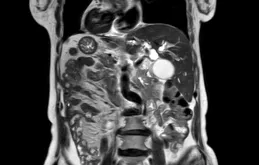

這部份最後,我們就用一個圖來簡要概括下常見顏色的便便及其對應的原因(圖2)。

圖2.常見便便顏色及主要原因(圖片來源:科普中國)